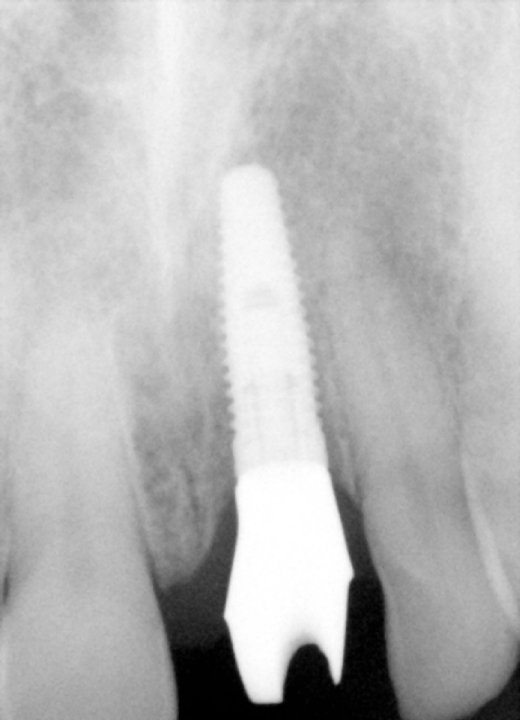

Final X-Ray Showing Implant

X-Ray Showing The Custom Abutment In Place